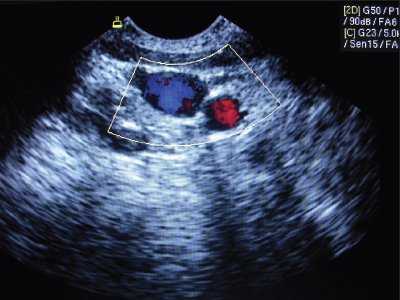

Статическая методика: контрольное УЗИ с визуализацией интересуемых сосудов выполнялось непосредственно перед пункцией центральных вен, разметка на коже наносилась до стерилизации операционного поля (рис.1). УЗИ проводилось в двух взаимно перпендикулярных плоскостях в поперечном и сагиттальном (продольном) сечении между ножками грудино-ключично-сосцевидной мышцы при исследовании внутренней яремной вены (рис. 2, 3) и в паховой складке при исследовании бедренной вены. С помощью предварительного УЗИ определяли глубину расположения вены от поверхности кожи, непосредственно ход венозного ствола, диаметр вены, диаметр артерии, взаимное расположение вены и артерии, степень сокращения (спадения) внутренней яремной вены на вдохе при наличии гиповолемического состояния.

Рис. 2. Нормальное расположение и размеры внутренней яремной вены и сонной артерии при исследовании в поперечном сечении.

Рис. 3. Нормальное расположение и размеры внутренней яремной вены и сонной артерии при исследовании в продольном сечении (сонная артерия находится глубже внутренней яремной вены).